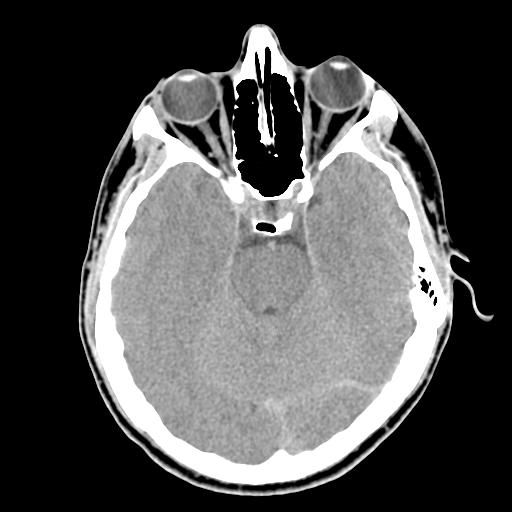

与伽马射线相邻的是大家相对熟悉的X射线,其被广泛应用于医学、天文、工业图像等。医学检查中的CT——计算机X射线断层摄影仪器,便是运用了X射线,其穿透人体时,能使人体组织在荧屏上或胶片上形成影像。基于X射线的穿透性、荧光效应和感光效应,以及人体组织之间的密度和厚度的差别,医生能够根据图像的颜色进行诊断。以下图头部CT图像为例,骨骼密度最高,因此吸收的X射线最多,因而在图像上呈现白色;肌肉和液体密度中等,所以吸收中等强度的X射线而呈现灰色,如大脑组织与眼球;气体和脂肪密度最低,所以吸收的X射线最少,因而在图像中显现为黑色或深灰色。